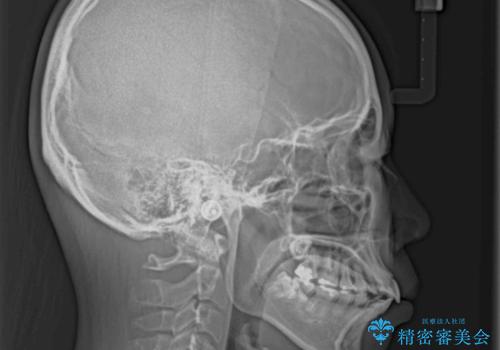

- 上下前歯を部分矯正したところ出っ歯になってしまったとのことで来院された患者様です。

上下左右第一小臼歯4本を抜歯して、積極的に口元を引っ込めるよう、ワイヤー装置にて矯正治療を行うこととしました。